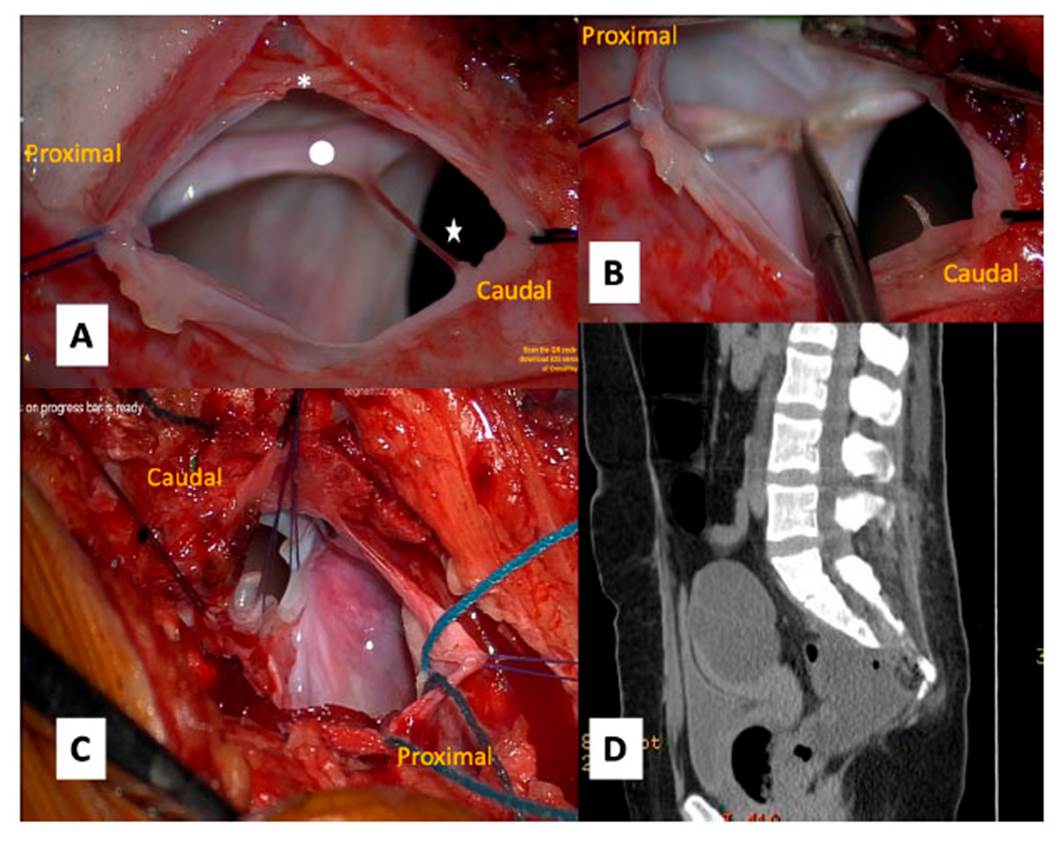

El tratamiento que se aplicó fue una laminectomía S1/S2/S3 y luego, con microscopio y monitoreo neurofisiológico de las raíces lumbares bajas y sacras, se seccionó el filum terminale. Después de comprobar que no había raíces dentro del saco herniario con el ostium a la altura de S3, el líquido cefalorraquídeo (LCR) se aspiró de la cavidad. Para terminar, el extremo proximal se liga al saco dural y el defecto óseo queda sellado con fascia muscular, injerto de duramadre y pegamento de tejido (Figura 3).

Luego de la cirugía, la paciente presenta retención urinaria. La estancia hospitalaria fue de 5 días, la herida se conservó en buen estado, la paciente no tuvo fiebre y fue dada de alta. La sonda urinaria se retiró a las 2 semanas. En la evaluación a los tres meses del alta, la paciente informó que el estreñimiento se mantenía, pero no las molestias abdominales, ni la cefalea a maniobras de Valsalva. En la tomografía de control persiste el 30 % del quiste, pero sin variación. En el control de 9 meses aún persiste una imagen de la masa anexial izquierda, la cual es extraída por Ginecología con el diagnóstico patológico de quiste anexial benigno.

Figura 3 Imágenes intraoperatorias. 3A Previa laminectomía S1, S2 y S3 con la duramadre abierta, se ven raicillas sacras bajas (*), filum terminale (punto blanco) y el defecto por donde se hernia el saco dural hacia ventral a nivel de S3 (estrella). 3B Previa comprobación por monitoreo electrofisiológico y coagulación térmica, se secciona el filum terminale para tratar la médula anclada. 3C Se procede a cerrar segmento proximal y caudal del saco para excluir el saco herniario. 3D Imagen de TC postoperatoria donde se evidencia saco residual del MSA y el quiste anexial izquierdo

Opciones de tratamiento de MSA

Las opciones de terapia son variadas y abarcan desde la observación, en los pacientes asintomáticos, hasta un abordaje quirúrgico anterior, posterior o combinado 3. El objetivo del tratamiento quirúrgico es ocluir la comunicación entre el meningocele y el saco dural para evitar las complicaciones. En los casos sin complicaciones, es seguro realizar un abordaje trans-sacro dorsal con el cierre del pedículo del meningocele. Los principios fundamentales del tratamiento quirúrgico son la delimitación del meningocele, el drenaje de su contenido, la reducción de los elementos neurales (si están involucrados en el saco), la escisión de cualquier tumor asociado y el cierre hermético del defecto dural 1. Rahimizadeh 7 logró una resolución completa del MSA con esta técnica. Recientemente, se describió el cierre laparoscópico transquístico transperitoneal del orificio del meningocele empleando clips de plástico 14. En la serie de Cheng et al. 1, diez de trece pacientes mejoraron sus síntomas a los seis meses del seguimiento, sobre todo, el estreñimiento.

El autor considera que el abordaje trans-sacro dorsal es factible, seguro y con menos complicaciones, por lo cual lo aplicamos en esta paciente. En este caso no se presentaron dificultades, salvo la retención urinaria temporal a causa de la manipulación de raíces sacras bajas.